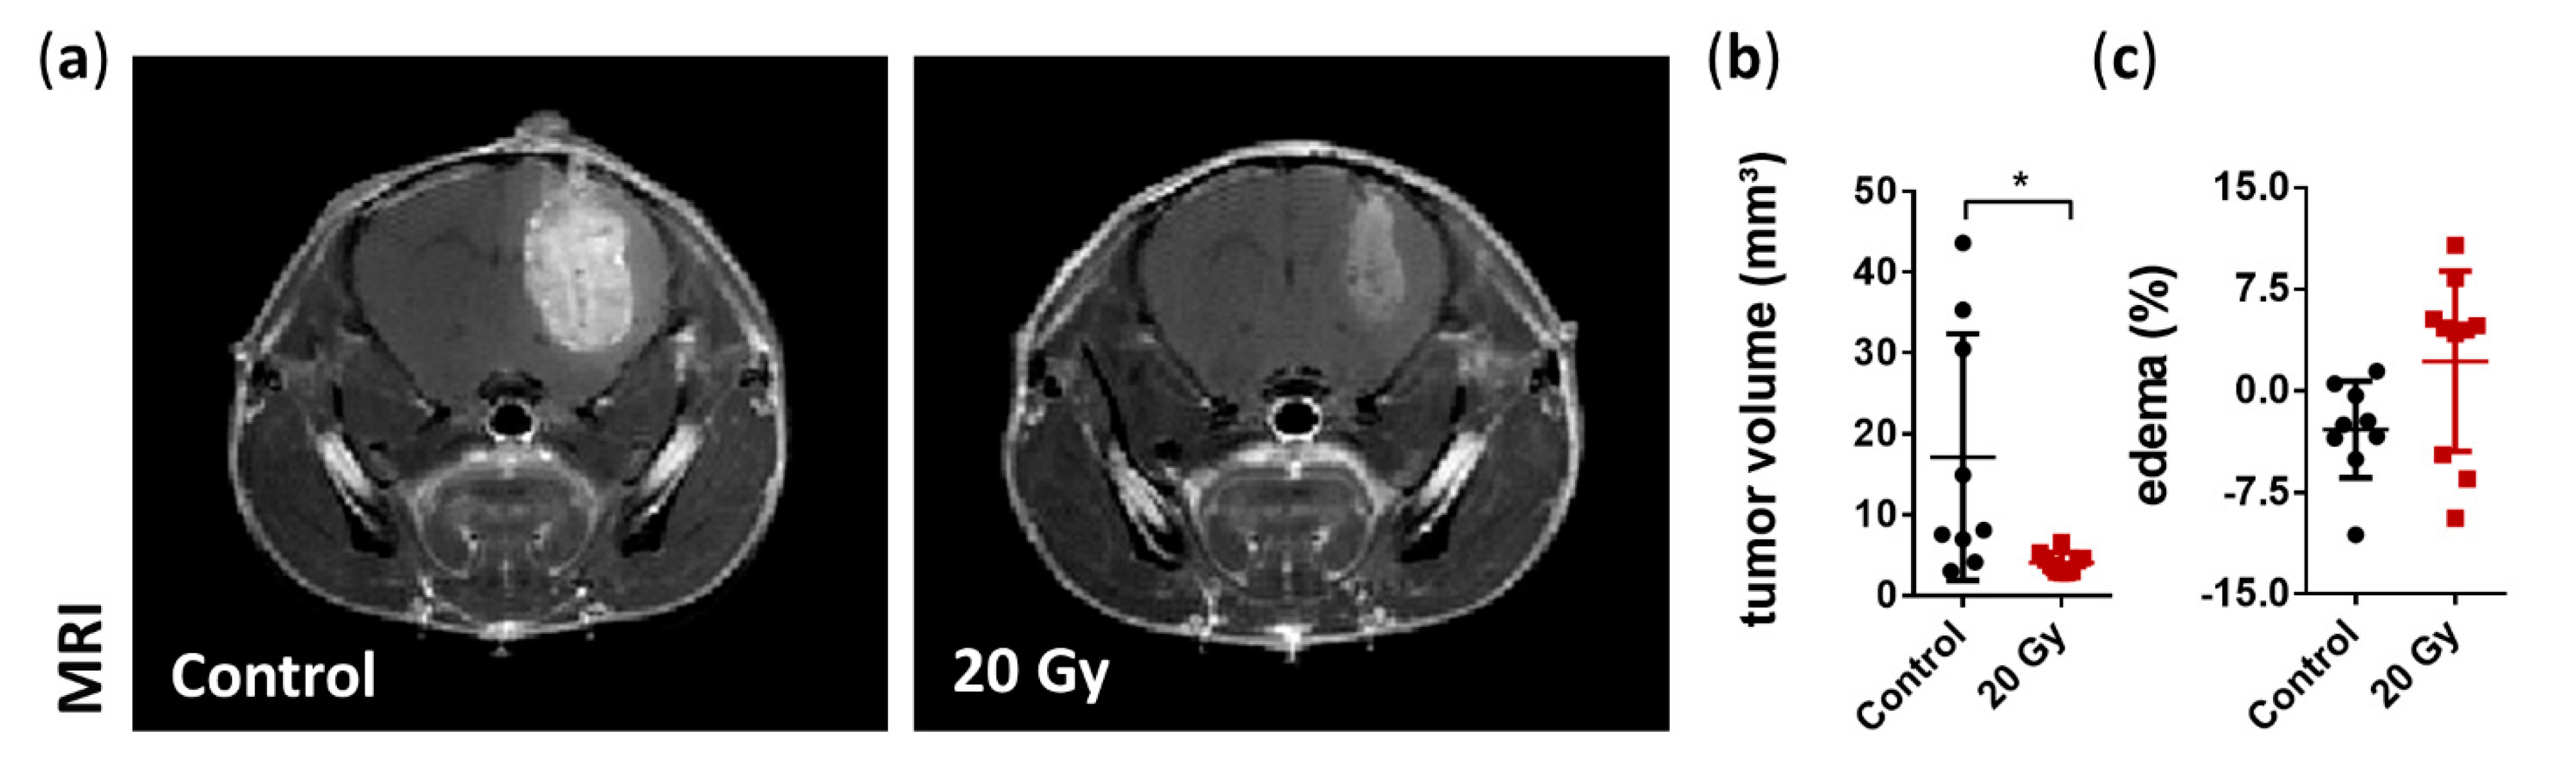

3.2. Assessment of Tumor Growth and Edema Formation

3.3. Assessment of the Early Effects of Irradiation Therapy